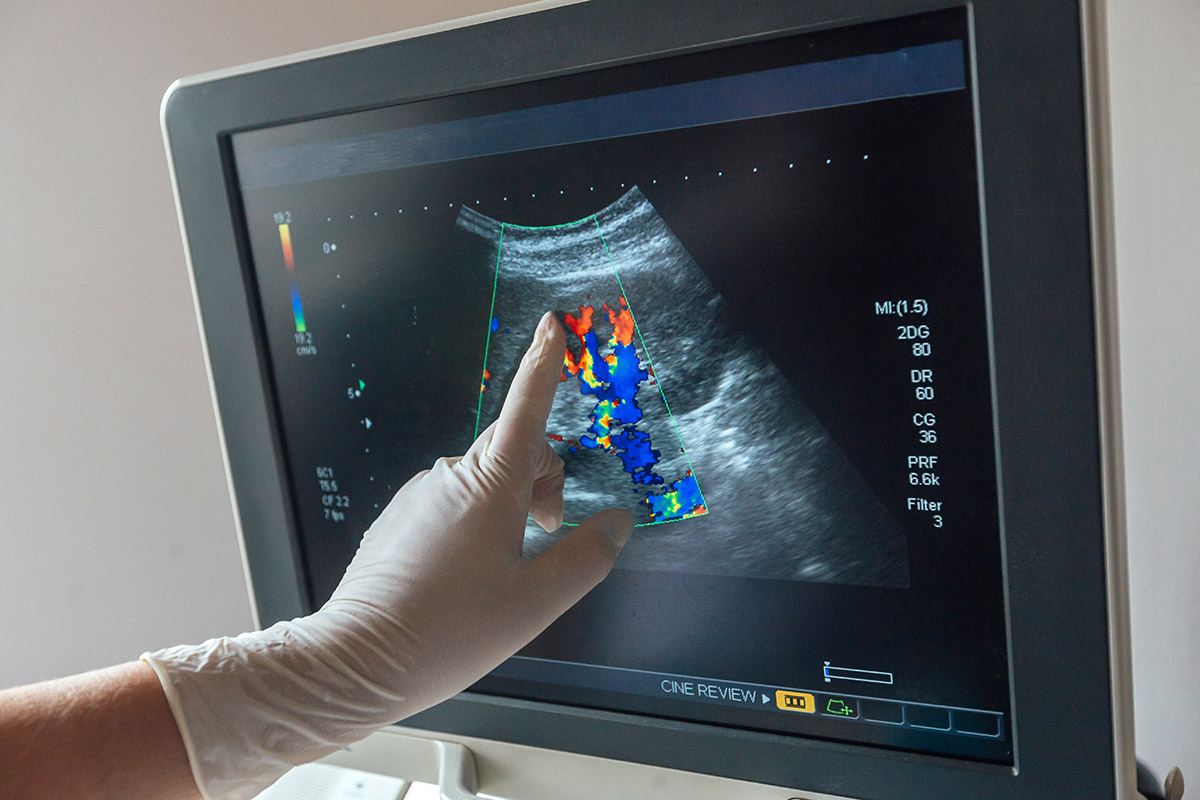

Суть метода заключается в применении ультразвукового сигнала, направленного к сердцу. Сигнал отражается от тканей и снова фиксируется датчиком. Затем сигнал поступает в эхокардиограф, где преобразуется в живое изображение, выводимое на экран монитора. Манипуляция дает возможность специалисту визуализировать основные структуры изучаемого органа, крупные коронарные сосуды.